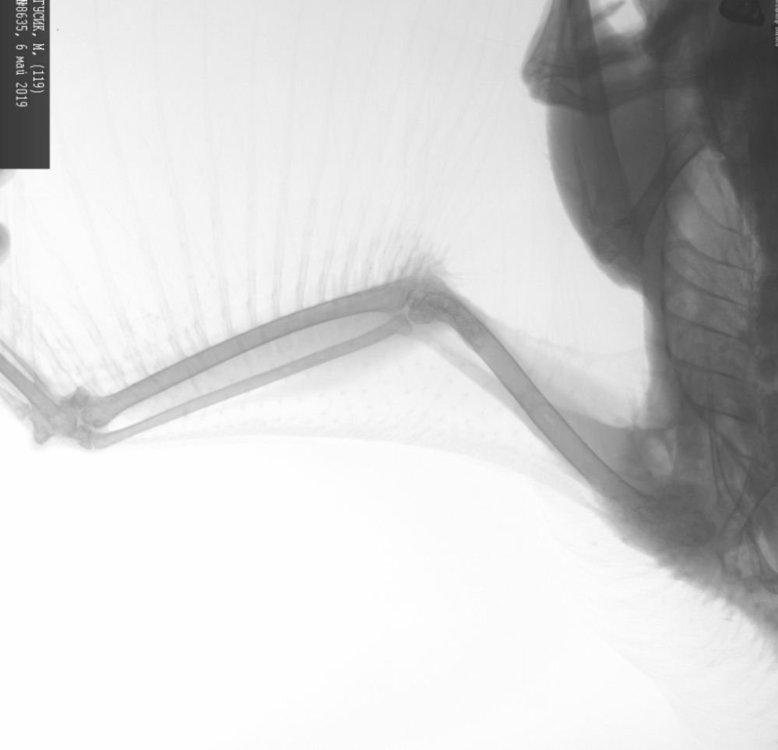

Гусь не раскрывает одно крыло

Здравствуйте, помогите пожалуйства. Уже неделю гусик не раскрывает правое крыло, улучшение было кратковременное и опять им не машет. совсем. и видно что ему больно, если крыло насильно раскрывать. Были у обычного ветеринара рядом с нами , сделали рентген- говорит крыло в порядке, переломов он не видит... предложил попоить траумель( Бад для людей). стоит он дорого, 1000р, на него денег нет.  что делать, как помочь птичке? может, есть какое-то противовоспалительное недорогое? правда, что там воспаление-лишь мое предположение...

Спасибо большое)) я еще успела раздобыть денег и дойти до травматолога, он сказал пить обезболивающее для собак. насчет крыла он тоже не знал, что там, но расстроил меня что надо гуся отдать и нового купить!! обалдеть предложеньице... Короче, мне наконец то посоветовали орнитолога недалеко от нас, пришли- показали птичку- действительно, нет перелома, но суставы надо лечить, ибо кормили комбикормом. я почему-то уверена была, что он не вреден и там есть все необходимое.. назначили много лекарств, будем пить. НПВС не надо, т.к. ему лучше не махать больным крылом.... Посмотрим, когда поправится..

Крыло оказалось сломано, по прошествии времени так и не смог гусик крыло полностью расправить. видать, так навсегда и останется..  Назначили лекарство для печени, по прошествии времени я забыла название, чтобы поддержать печень, которая пострадала от комбикорма. Расписали конкретно что порациону для гуся можно-нельзя, в итоге мы отменили комбикорм и предлагали гусю всевозможные  овощи-фрукты-травы-зерна. Ничего из предложенного он не пожелал кушать. Мне пришло в голову попробовать прорастить пшеницу и попробовать дать. чудо!  Гусь согласился это  съесть. больше ничего не хочет. теперь на пророщенной пшенице сидим..